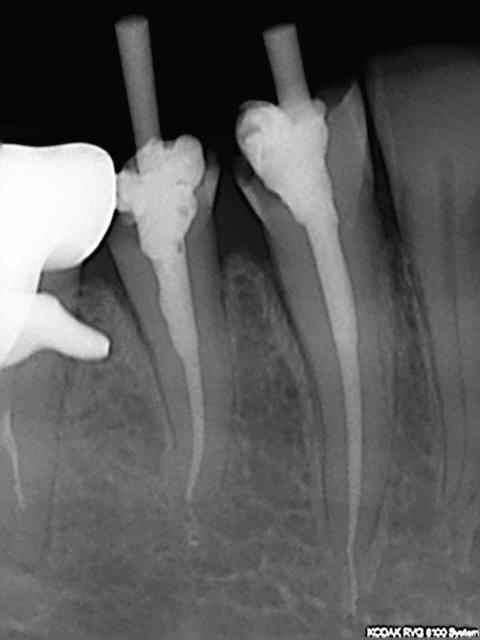

Non, en fait j'en fais une 50 aine par mois, un peu plus de 2 par jour.

En général la rapidité d'un acte dépend du nombre d'instruments rotatifs en fonction, ça évite de perdre un temps fou en changeant les fraises et les limes, et bien évidemment d'une assistante au fauteuil bien rodée (cf le post 15 mn endo molaire). Je n'ai pas l'assistante au fauteuil dommage !)

Je ne fais pas le topo sur la cavité d'accès que j'ai cependant tendance à faire bien large pour accéder aux entrées canalaires facilement.

A partir de là tous les instruments d'endo sont au préalable en place sur un instrument rotatif. Sx protaper sur l'entran, largo numéro 3 sur double bague verte, s1 protaper sur endomaster, r25 réciproc sur wd silver, SAF (pas tout le temps vu les 50 euros de l'instrument jetable) Endo activator ou rinsendo plutôt ngap oblige !)

Je fais la recherche des canaux avec l'entran et le sx que j'essaye de faire progresser le plus possible en direction apicale (sans forcer comme un bourrin, hein !) puis ouverture au largo de l'entrée canalaire et re-sx pour progresser encore jusquà environ entre 15 et 20 mm de lt (dépend de la longueur estimée de la racine à la radio pré op et de sa perméabilité). Ensuite passage du s1 avec l'endomaster qui en général descend à la lt sans problème (réglage de l'endomaster à -0.5mm lt).Stop sur le r25 qui descend sans problème à la lt. Irrigation tout au long de la procédure évidemment (sauf s1 car la lt ne peut pas etre déterminée avec l'endomaster si trop de dakin). Récapitulation si problème à l'une des étapes mais c'est rare.

Radio cone 25 en place etc....)))) j'avoue je pèche dans le etc !)))

"Le" gros plus ces derniers mois a été l'apparition du r25 réciproc qui a permis de supprimer les s2,f1, f2 protaper et ce sans casse ni fausse route à ce jour ! une révolution en rupture de stock en ce moment.))))

Mise en forme entre 2 et 5 mn par canal.

humm, les endo dans la salive en 10-15 minutes, sauf chico29 et quelques autres, les résultats que je vois sont dignes de gens plus intelligents et créatifs c'est certain...

A voir les radio sur nonol, des bouches avec 10-12 endo, et 7-8 belles lésions, bref, tout est normal, on verra dans 1 ou 2 ans...ah madame, vous faites des kystes...c'est comme cela